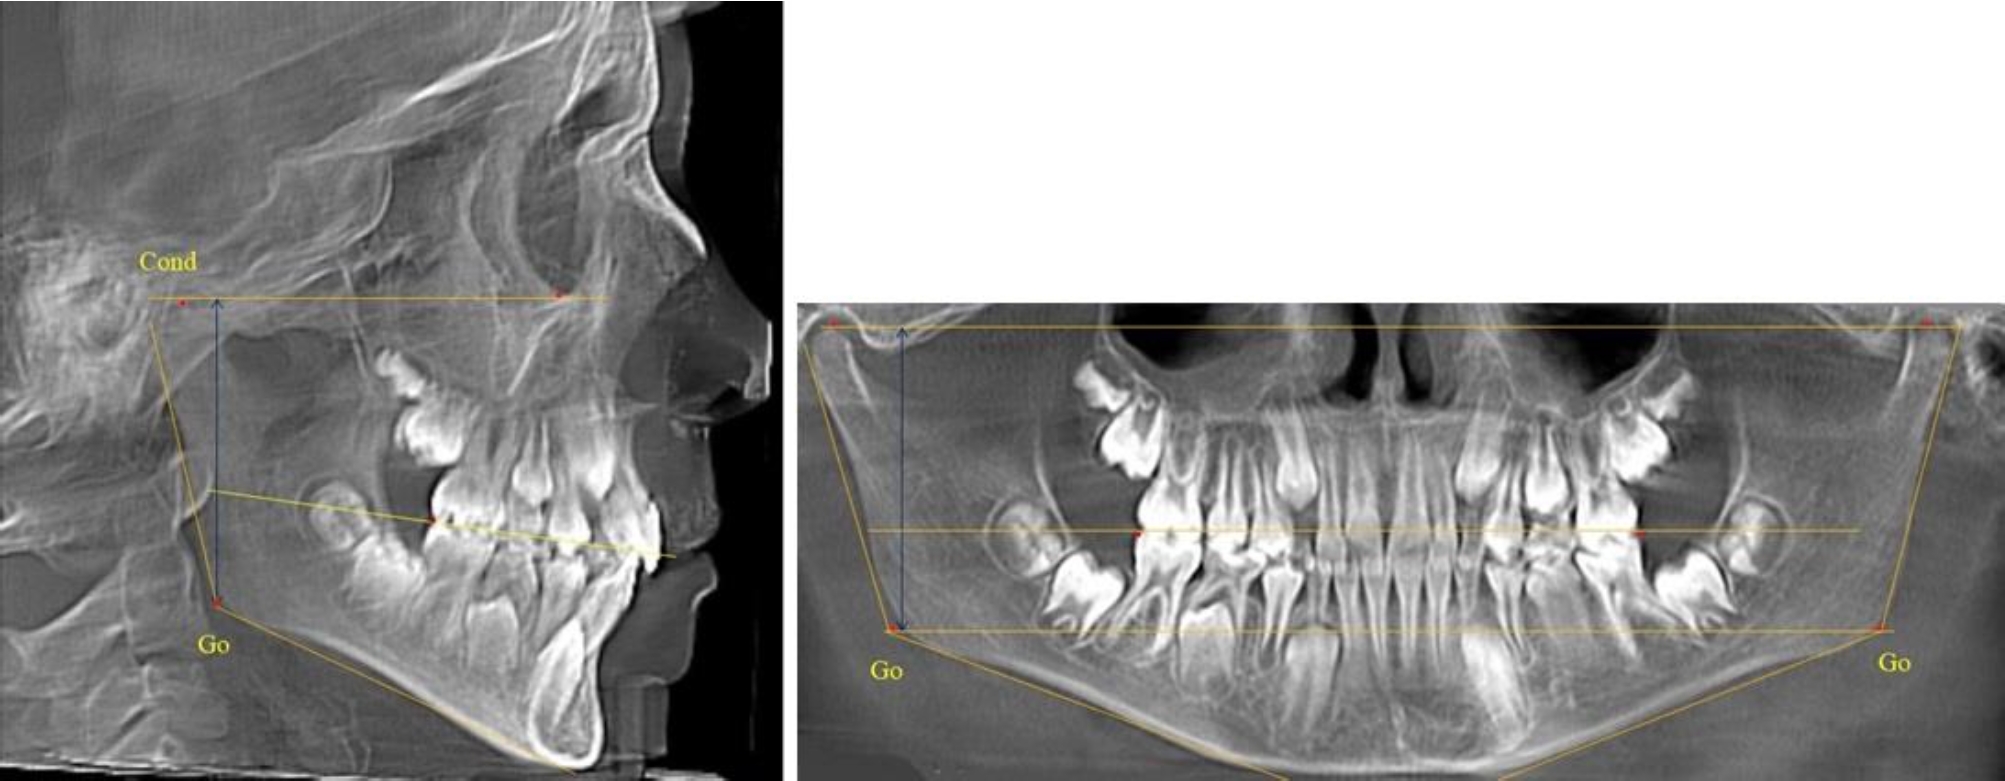

Во 2-й группе были проанализированы 11 телерентгенограмм и 11 ортопантомограмм, что составило (10,38 ± 2,96) % от числа изученных рентгенограмм. На всех рентгенограммах первые постоянные моляры были установлены в окклюзии, и произошла смена нижних медиальных резцов.

На всех парах рентгенограмм угол нижней челюсти, измеренный на телерентгенограмме, так же, как и в 1-й группе, соответствовал углу, полученному при построении угла на ортопантомограмме. Окклюзионная линия делила ветвь на два отдела (рис. 2).

Рис. 2. ТРГ и ОПТГ пациента после прорезывания первых постоянных моляров

Как на ортопантомограмме, так и на телерентгенограмме высота ветви у детей 2-й группы составляла (46,54 ± 2,87) мм, что было несколько больше, чем у детей 1-й группы (р ˂ 0,05). При этом высота верхней окклюзионно-суставной части была (25,42 ± 1,59) мм, а нижней – (21,12 ± 1,77) мм.

Таким образом, верхняя часть была несколько больше нижней, что и определяло рост обеих частей ветви.

Относительные показатели соразмерности частей ветви нижней челюсти показали, что отношение высоты верхней части ветви к нижней в среднем составляло 1,21 ± 0,12. Отношение общей высоты ветви к верхней ее части составляло 1,83 ± 0,13, а отношение общей высоты ветви к нижней ее части было 2,20 ± 0,16, и достоверных различий по относительному показателю отношения всей высоты к верхней и нижней челюсти нами не отмечено (р ˃ 0,05).